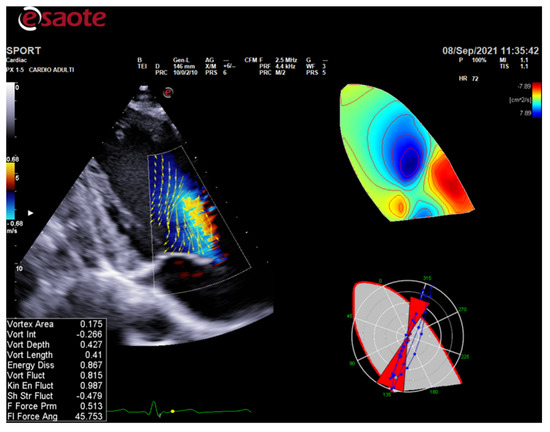

Cardiac magnetic resonance (CMR) is the second most valuable imaging method for the differential diagnosis between physiology and pathology in athletes. It can help discriminate health from disease where echocardiography leaves doubts.

CMR is the gold standard for the definition of myocardial morphology, wall motion assessment, heart chambers size, and tissue characterization. It evaluates, with high accuracy and reproducibility, the heart chambers’ volume and mass, as well as global and regional contractile function [58,59,60]. It is the method of choice for the accurate evaluation of right ventricle morphology and function (Figure 4 and Figure 5).

Figure 4.

Cardiac magnetic resonance in an endurance athlete (long-distance swimmer). A symmetric dilatation of both right and left ventricular chambers is clearly depicted in 4-chamber (left panel) and 5-chamber (right panel) views. AO: aorta; LV: left ventricle; RV: right ventricle.

Figure 5.

Cardiac magnetic resonance in a top-level power athlete (weightlifter). A significant harmonic and symmetric wall thickening is documented in 4-chamber (A), 5-chamber (B), 2-chamber (C), and short-axis (D) views. AO: aorta; LV: left ventricle; RV: right ventricle.